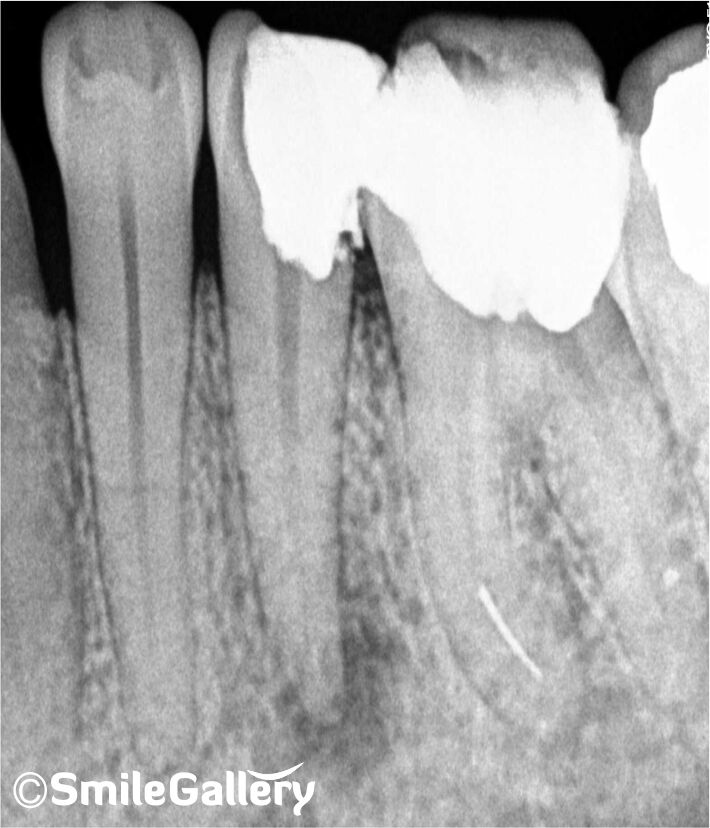

When the pulp is affected, root canal therapy is crucial. Inside, a tooth becomes infected or damaged due to decay or trauma. Addressing this issue promptly is crucial to prevent further complications and preserve the affected tooth. Finding a reputable dental clinic offering Root Canal Treatment Near me is vital when experiencing dental pain or discomfort.

For residents of Bhopal, it is conveniently located and offers expert root canal treatment. Their skilled dental professionals are trained to provide efficient and pain-free root canal procedures to alleviate your dental issues. Their advanced equipment and compassionate care ensure that your root canal treatment is a comfortable and successful experience.